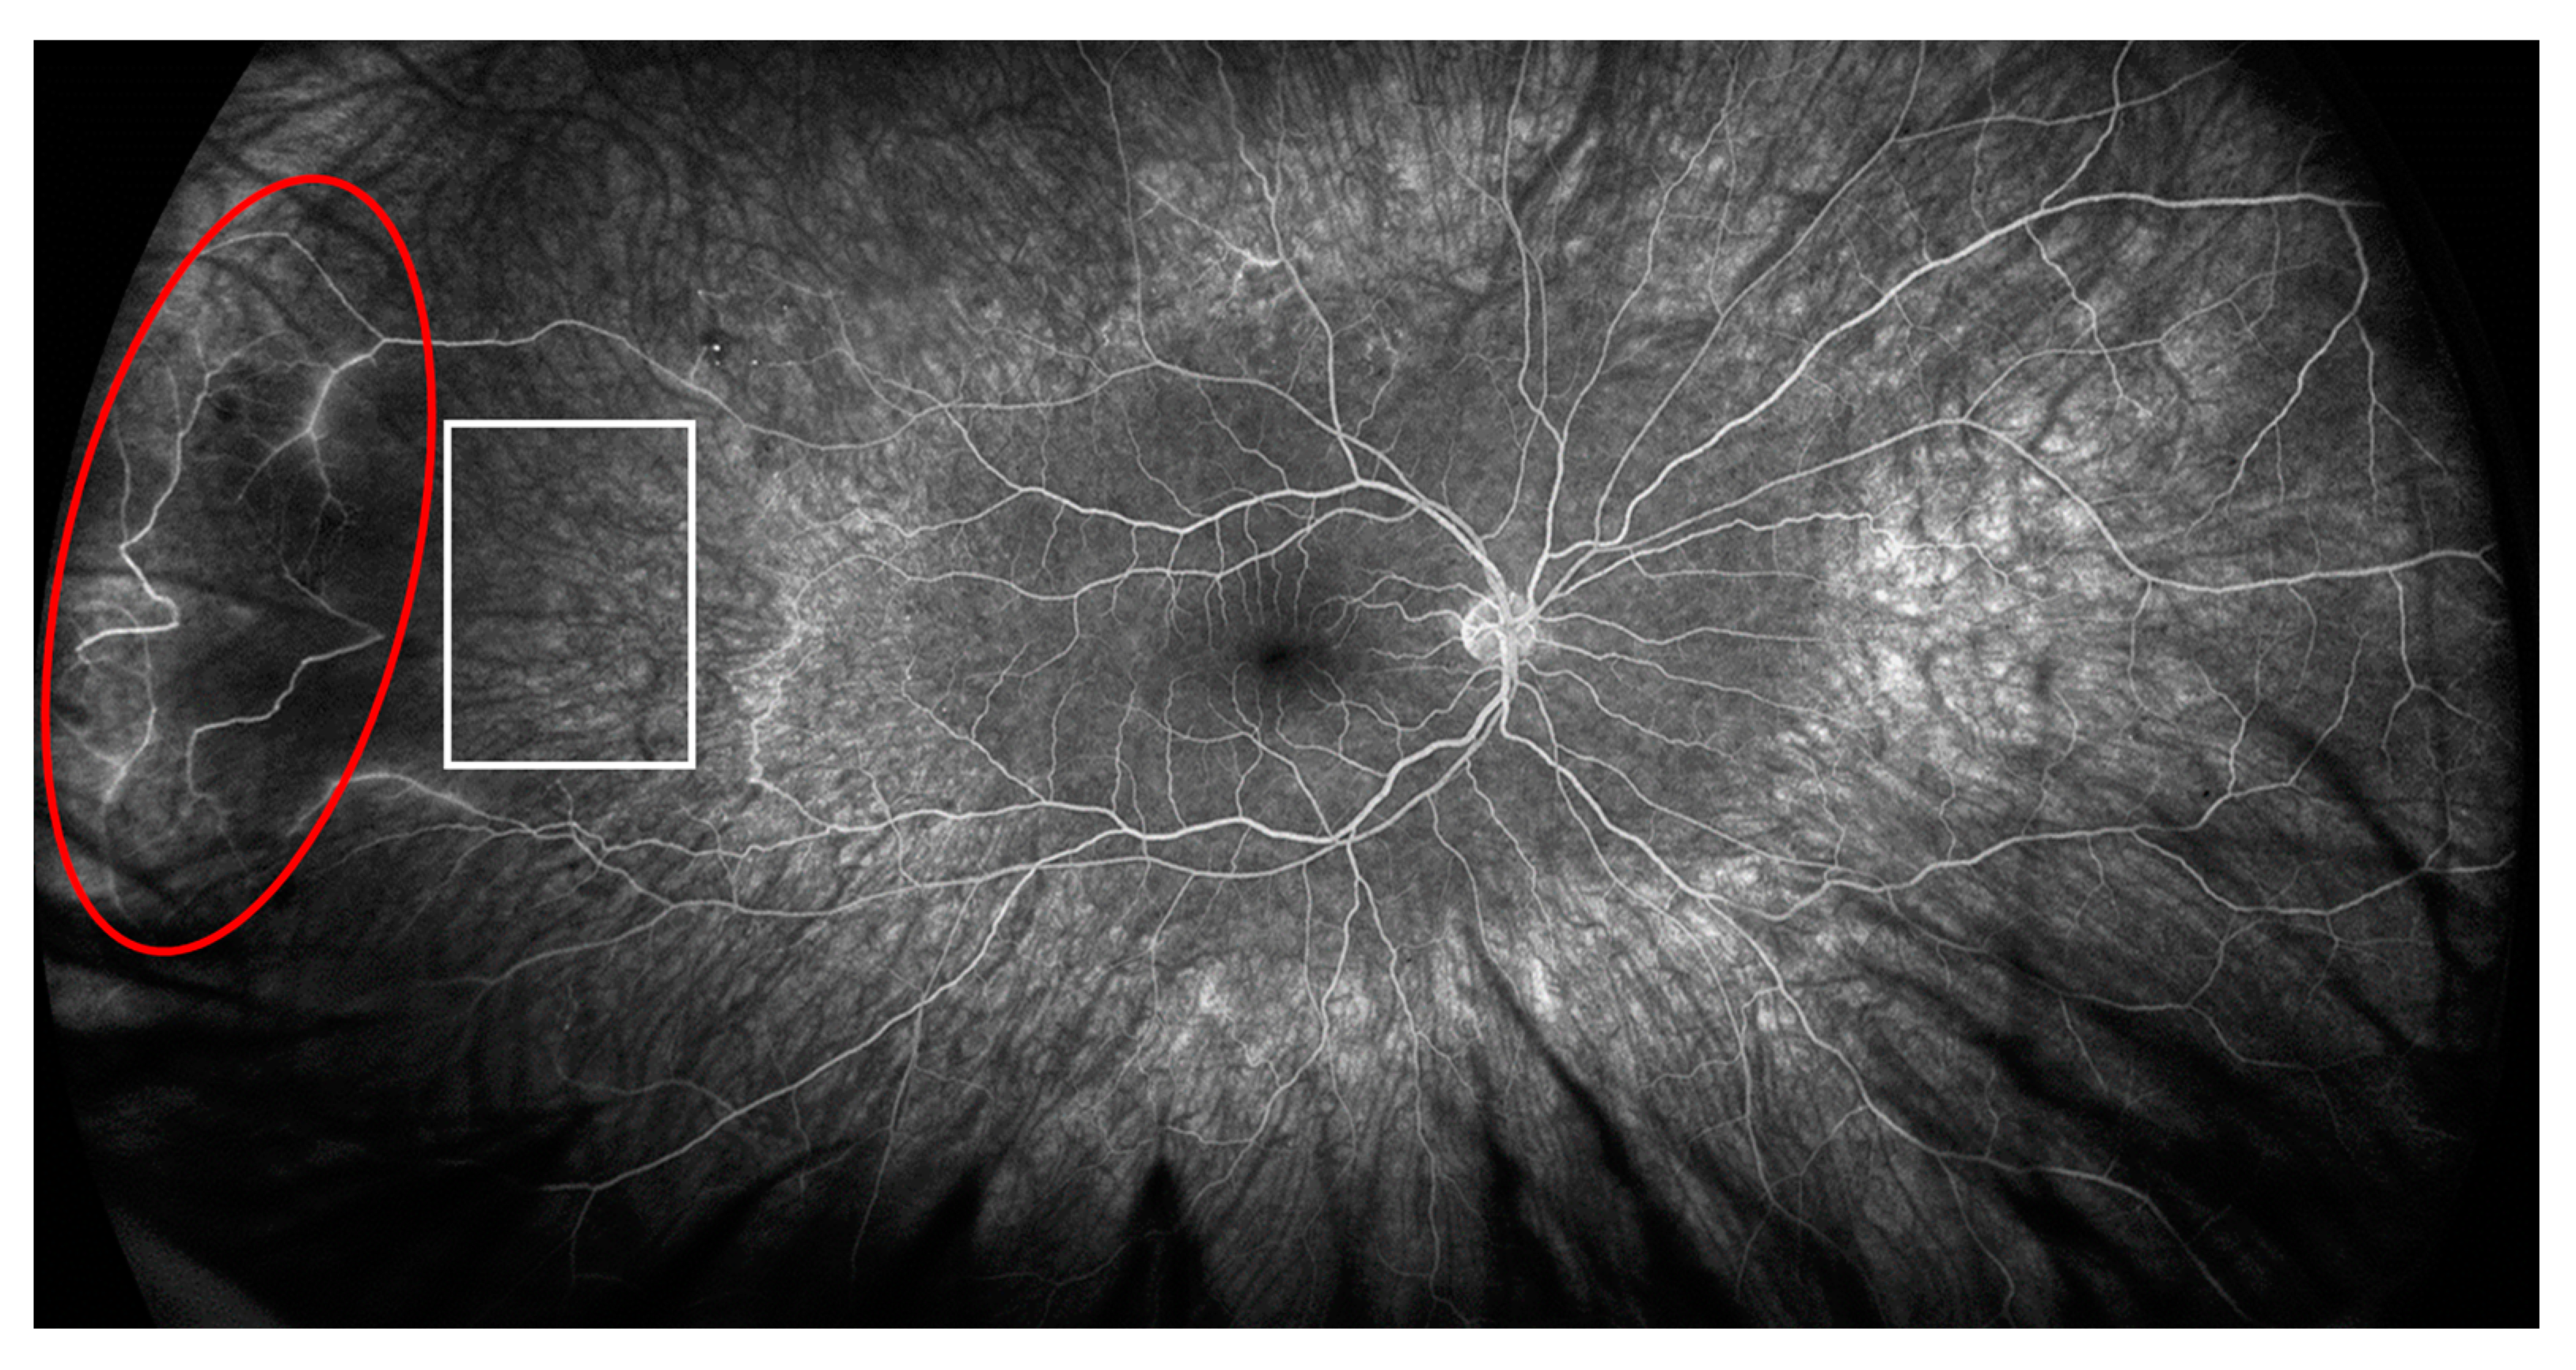

2. Case Description